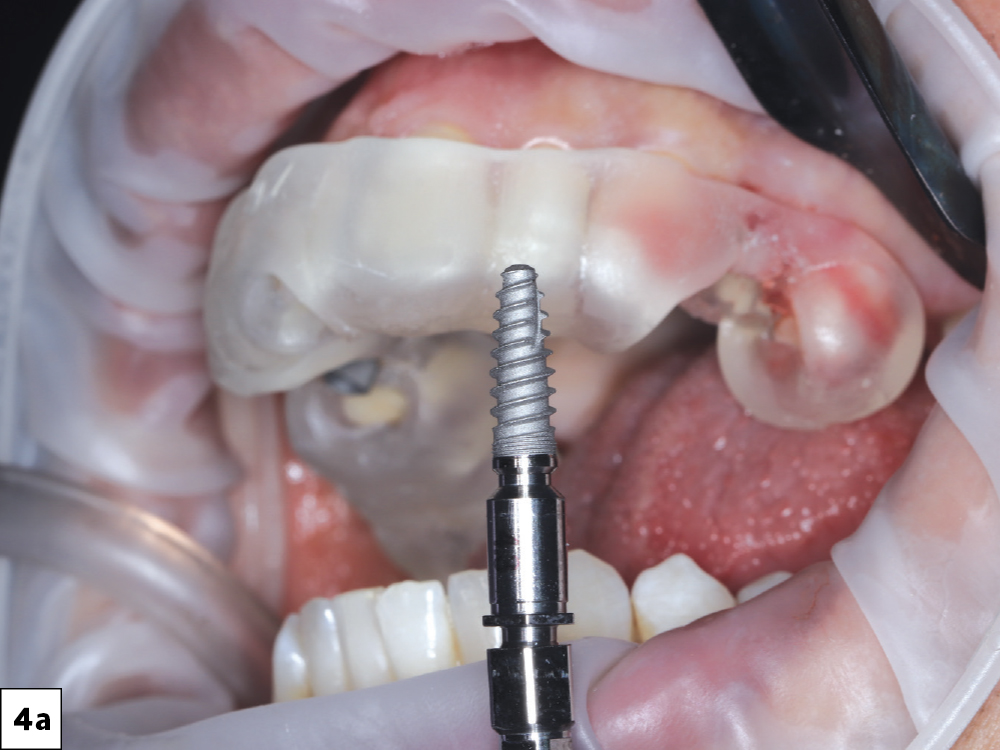

Surgery was performed under local anesthesia with the printed guide securely seated for full control of angulation and depth

Two Glidewell HT™ Implants (Glidewell Direct; Irvine, Calif.) were placed according to the digital plan, achieving excellent primary stability-b

Two Glidewell HT™ Implants (Glidewell Direct; Irvine, Calif.) were placed according to the digital plan, achieving excellent primary stability-c

Figures 4a–4c: Surgery was performed under local anesthesia with the printed guide securely seated for full control of angulation and depth. Two Glidewell HT™ Implants (Glidewell Direct; Irvine, Calif.) were placed according to the digital plan, achieving excellent primary stability.